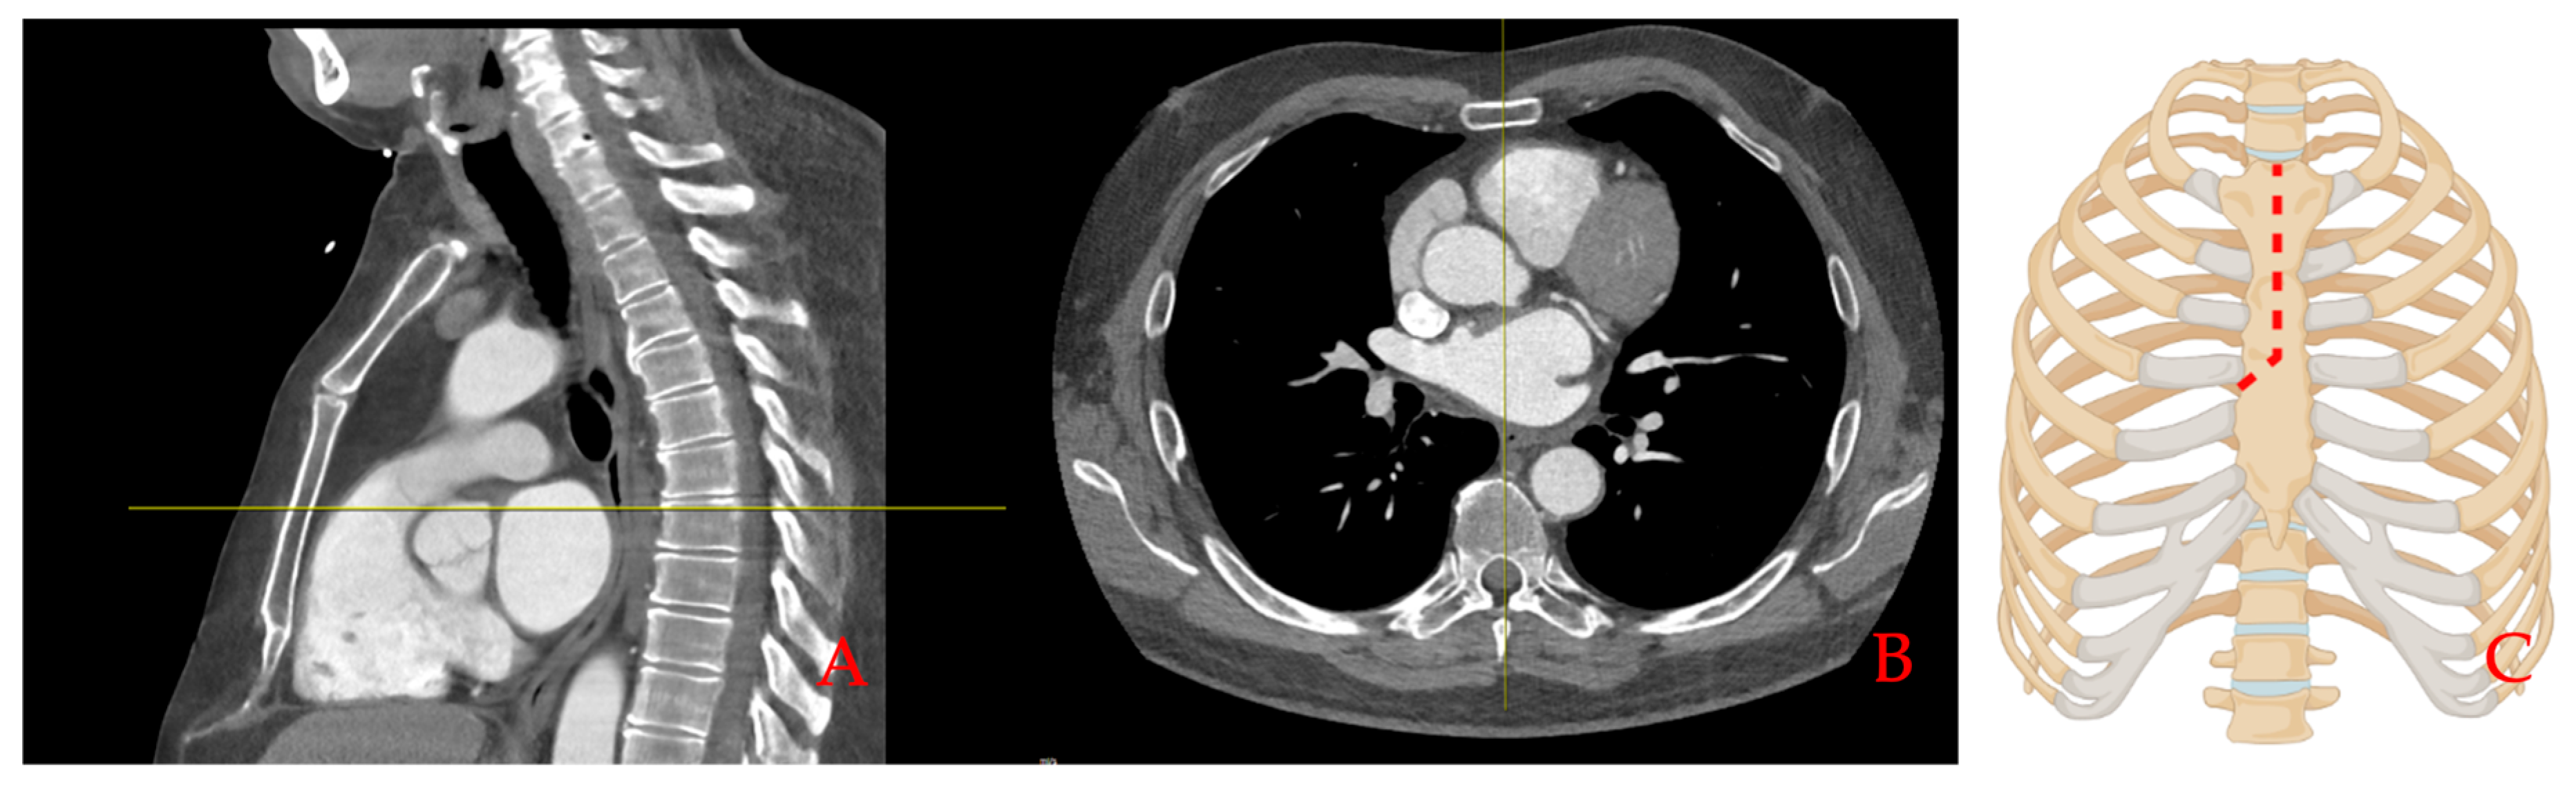

2.2. Surgical Technique

2.2.1. Minimally Invasive Cardiac Surgery

2.2.2. Sternal Closure Using Rigid Plate Fixation